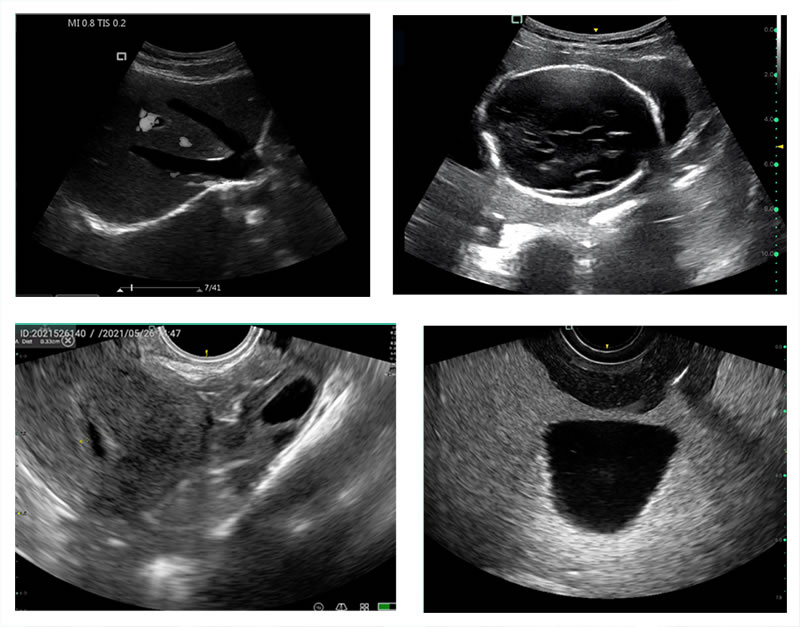

Режим изображения: B, B & M, 2B, PW

Частота зонда: 2 - 12MH